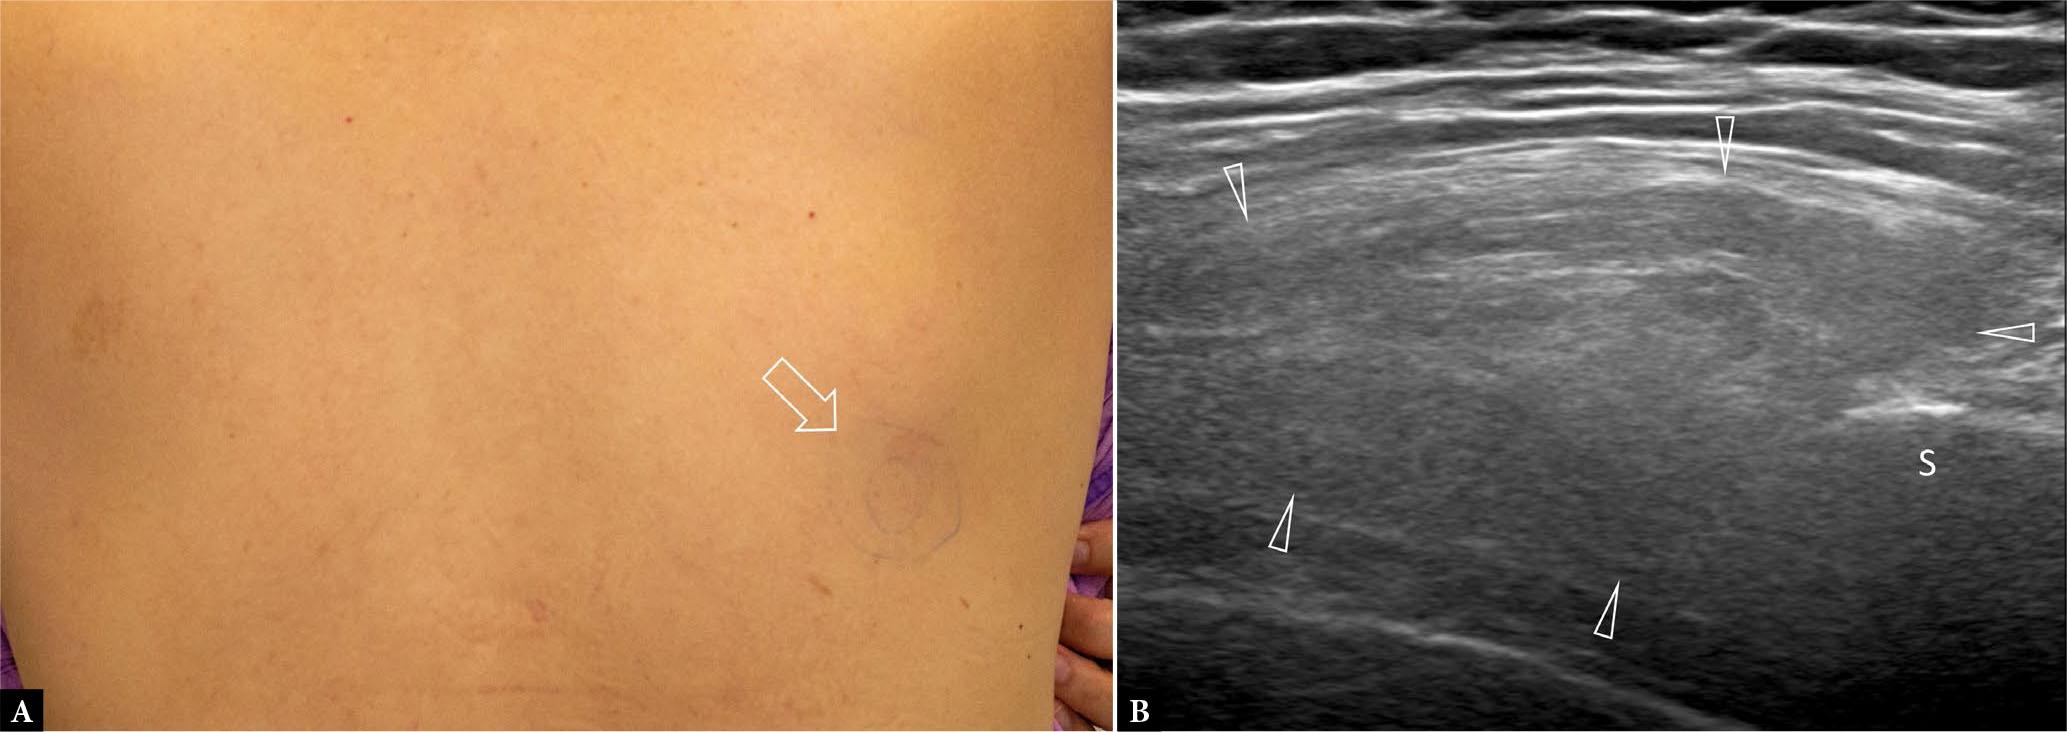

Fig. 2.

56-year-old female with discomfort and swelling in the infrascapular region. A. Clinical photograph shows site of swelling (arrow) marked by the patient prior to US examination. B. Transverse US shows a large mass with alternating hypoechoic bands (which are compatible with fibrous tissue) and hyperechoic bands (which are compatible with fatty tissue) at the inferior tip of the scapula (S). The mass was mildly compressible. No tumor vascularity was present on color Doppler imaging (not shown). This fibrolipomatous-type mass (arrowheads) is consistent with elastofibroma dorsi